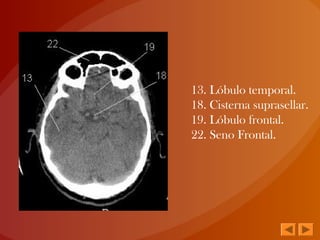

13. Lóbulo temporal.

18. Cisterna suprasellar.

19. Lóbulo frontal.

22. Seno Frontal.